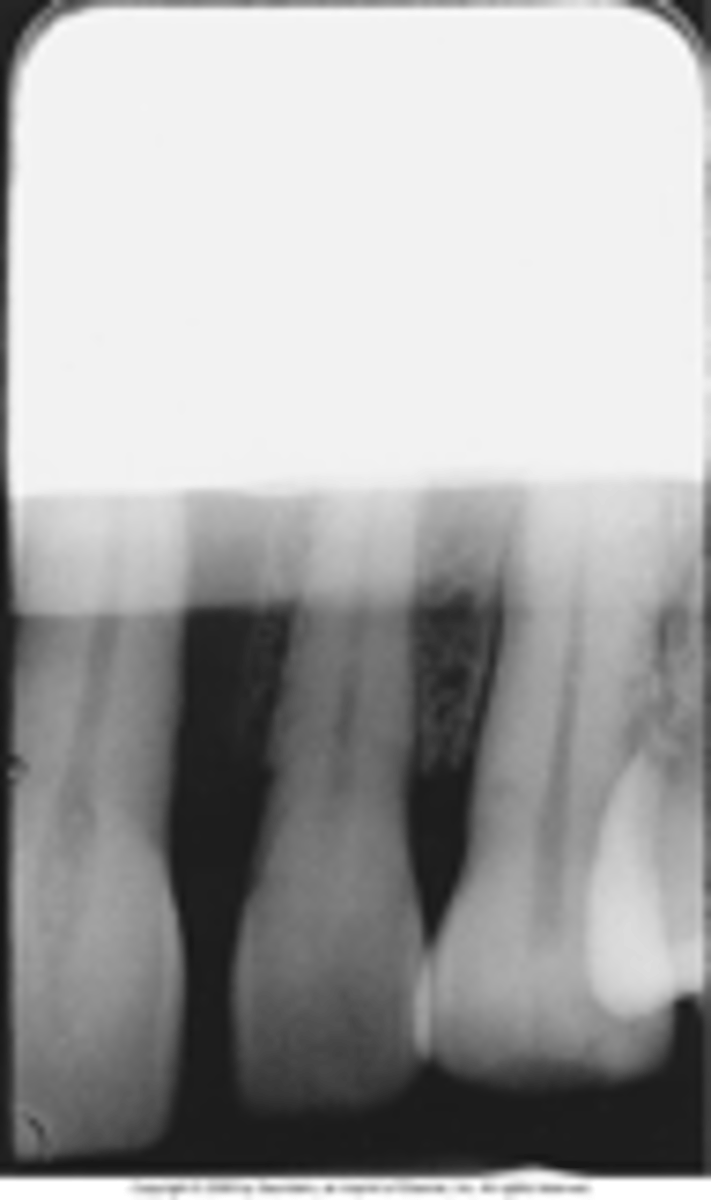

Developer cut off

A straight white border due to underdeveloped portion. Film not completely immersed in developer.

Fixer cut off

A straght black border, film not completely immersed in fixer.